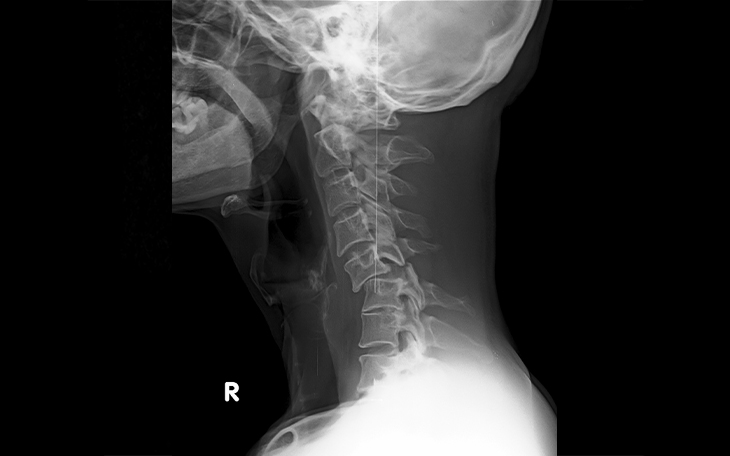

Ein einfaches Röntgenbild der Wirbelsäule zeigt nur die Knochenstruktur, nicht jedoch die Bandscheiben oder Nerven. Für eine exakte Diagnose wird daher ein MRT (Magnetresonanztomographie) empfohlen. Es ist nicht-invasiv und zeigt die betroffene Bandscheibe deutlich. Vor der Verfügbarkeit des MRT wurden CTs oder Myelogramme genutzt. Bei Patienten mit Herzschrittmachern, die kein MRT machen dürfen, müssen diese Verfahren weiterhin eingesetzt werden.

• Röntgen (Standard): Erste Wahl bei Verdacht auf Fraktur oder Instabilität

Die Diagnose basiert auf einer gründlichen Anamnese und körperlichen Untersuchung. Röntgenbilder können Arthrose zeigen, liefern jedoch keine ausreichenden Informationen zur Rückenmarkskompression. Eine MRT ist das Mittel der Wahl zur Beurteilung des Ausmaßes der Stenose. Bei Patienten mit Herzschrittmacher oder MRT-Kontraindikationen sind CT-Myelogramme eine Alternative.